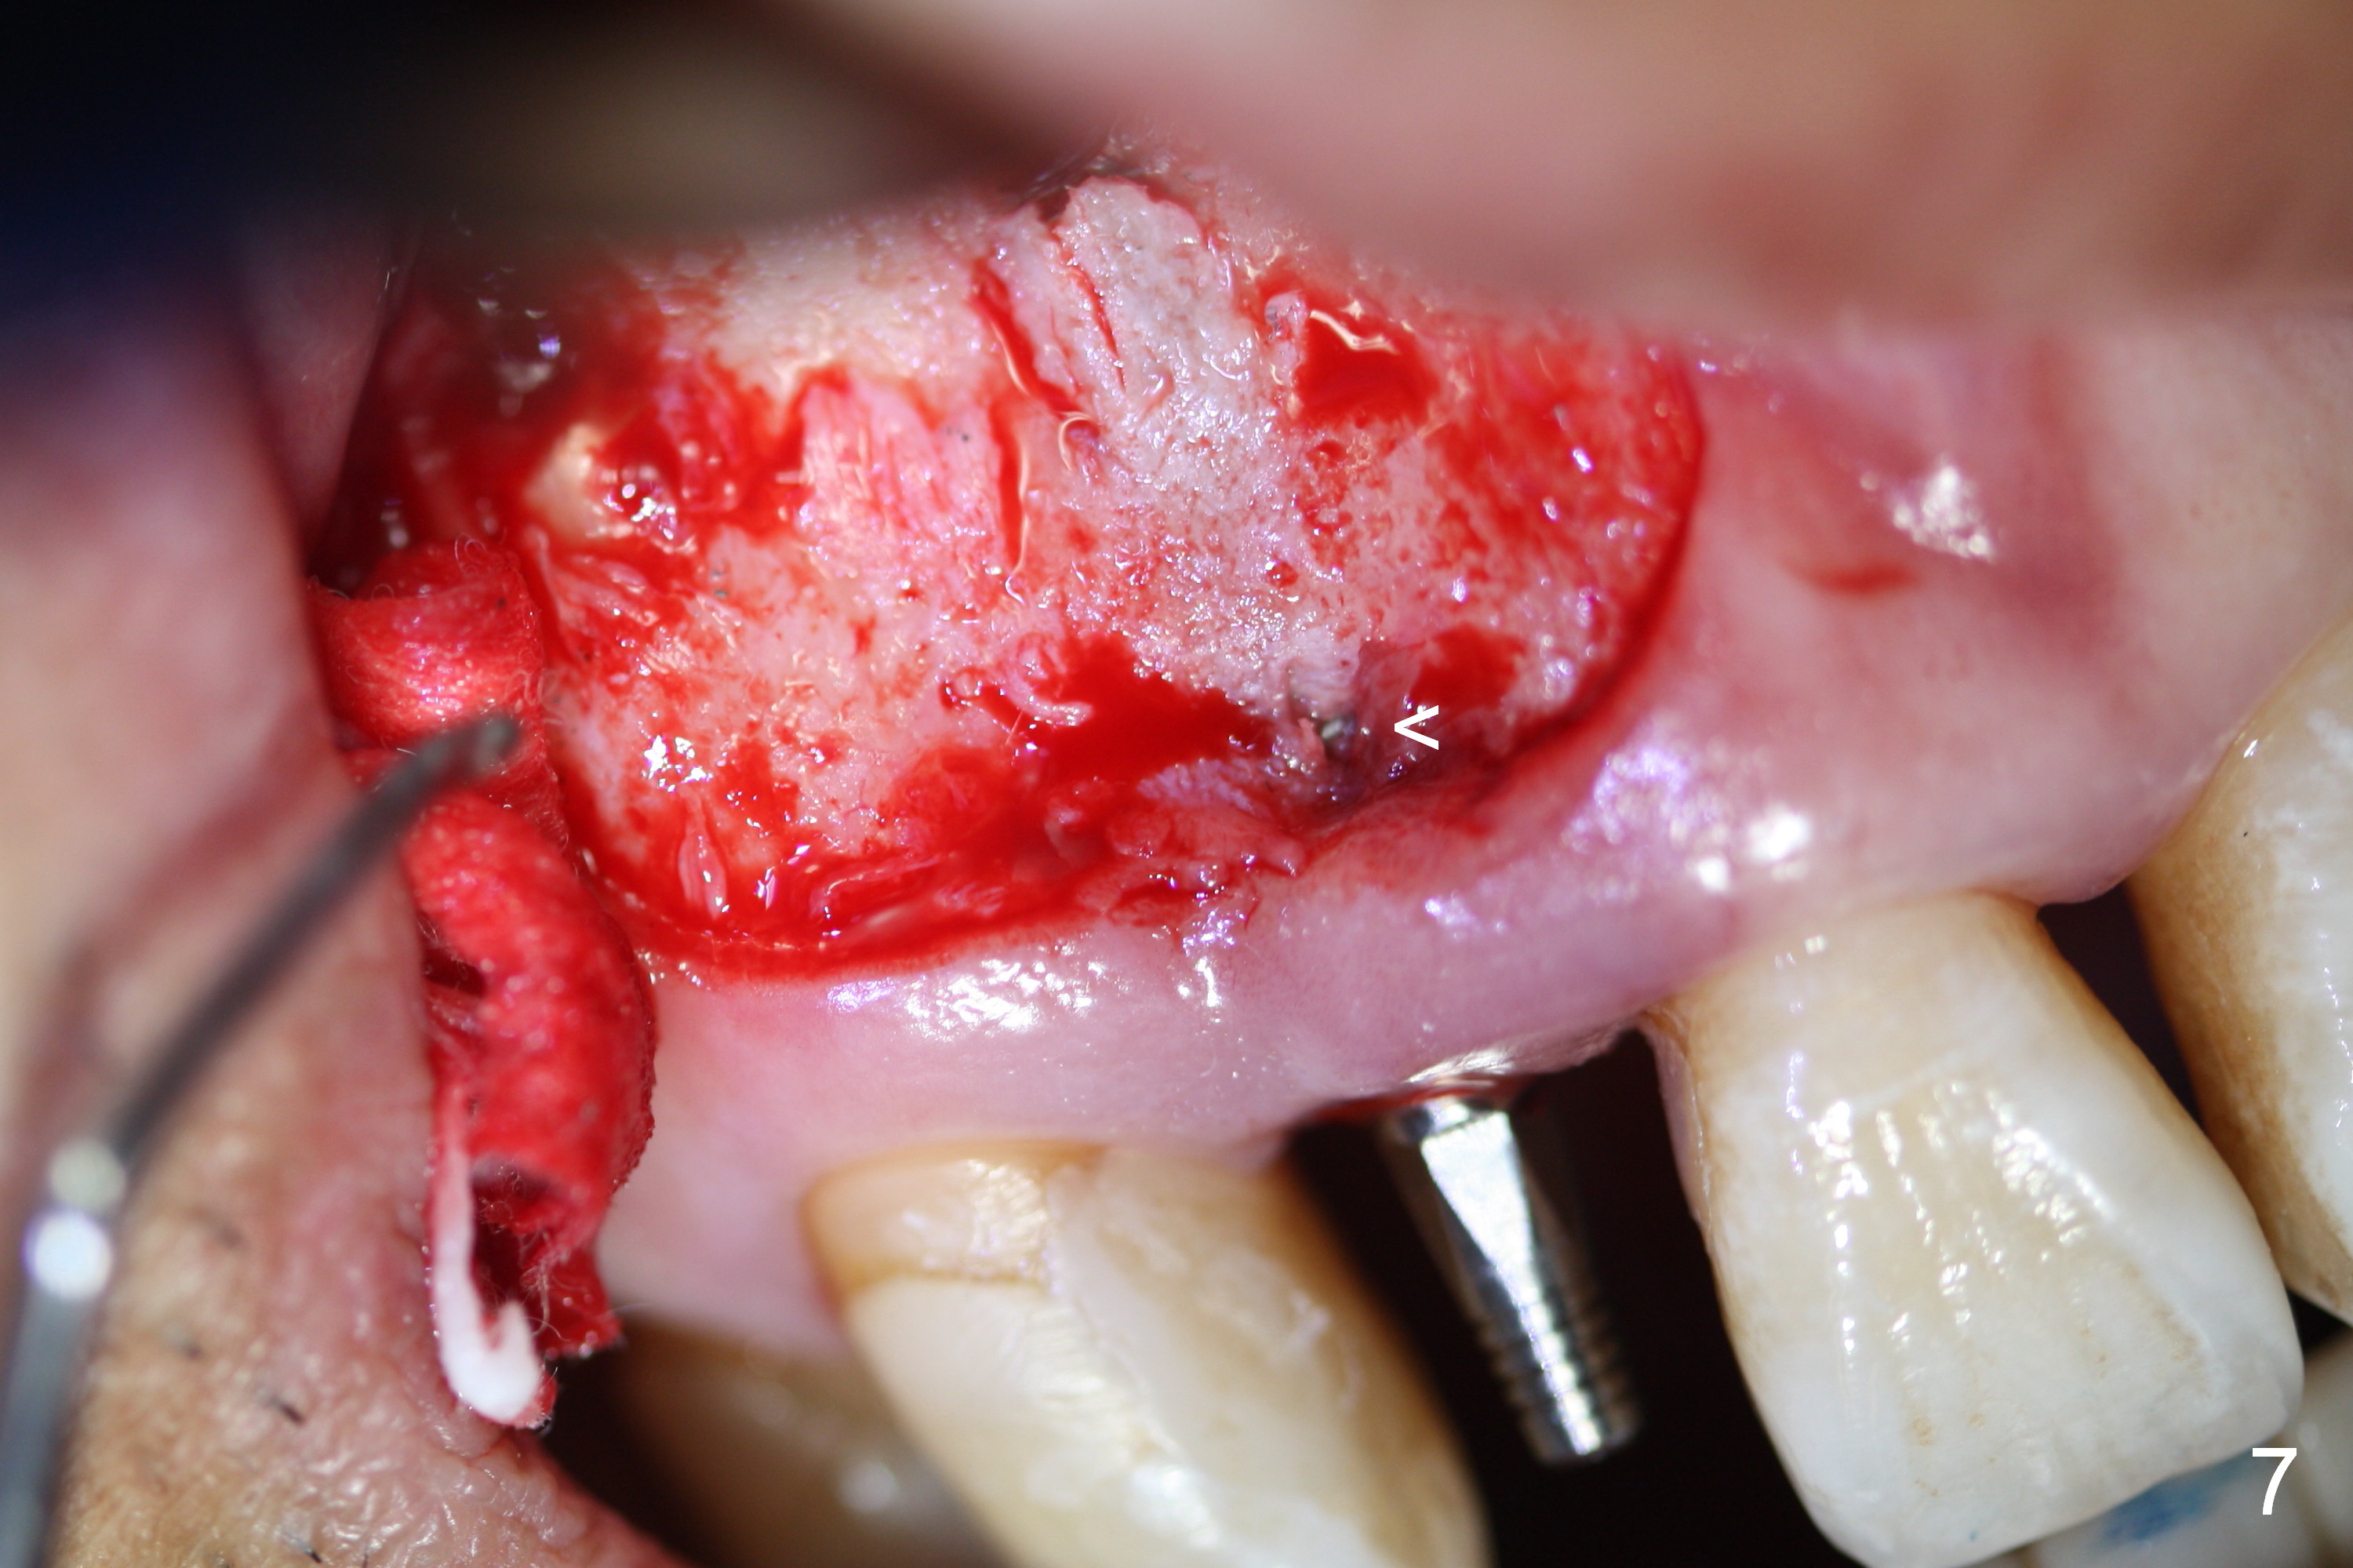

Apical Buccal Plate Perforation

Preop exam shows the apparent wide ridge at #7 (Fig.1). What is ignored preop is the concavity in the apical buccal region (Fig.2 *). When a 3x16(4) mm 1-piece implant is being placed (Fig.3 *, flapless), the apical buccal plate vibration is felt. The biggest mistake is that initial osteotomy is ~ 6 mm shy of the implant length, partially because of 6 mm gingival height. Since the tooth #6 is symptomatic after RCT with paste overfill (Fig.4 >), apicoectomy is contemplated at #6 with exploration of the buccal plate at #7 (Fig.5). Since the implant appears to be long enough, implant apical resection is performed (Fig.6). Since there is coronal thread exposure due to previous periodontitis (Fig.7 <), bone graft is placed in these 3 defective areas after decortication.

Extending the initial osteotomy to the full length of the implant is critical. If perforation is detected early, the trajectory can be changed. Incision should be made if there is no CBCT study. The incision heals 1 and 4 weeks postop (Fig.8,9). The patient returns for final restoration 6 months postop. Apical defects appear to have healed at #6 and 7 (Fig.10,11). Fig.12 is taken 11 months postop and 5 months post cementation. The patient has an accident 9 months post cementation. In fact the implant is alright, while the tooth #6 fractures and #8 subluxates.